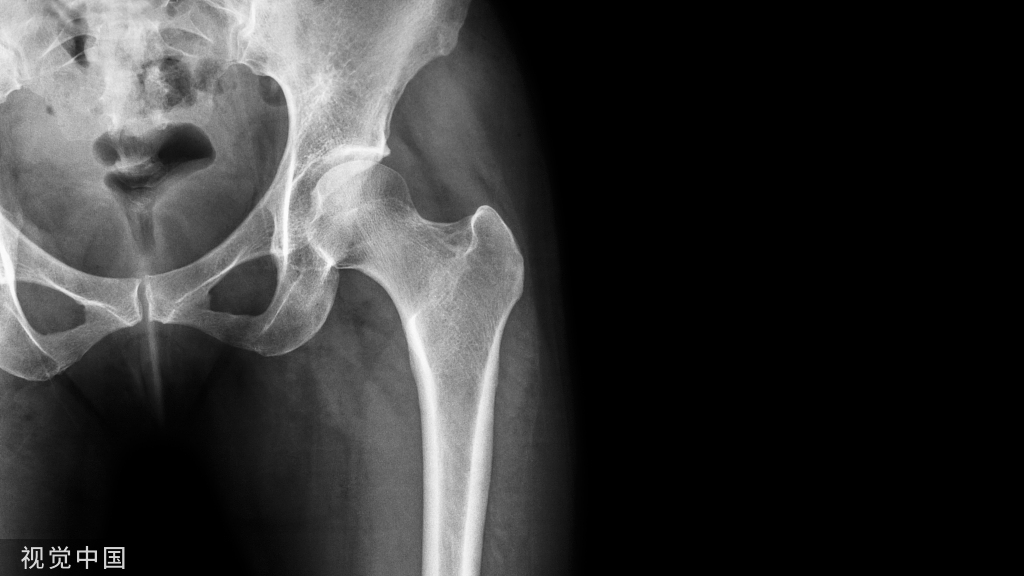

布鲁氏菌性脊柱炎早期X线表现 L3/L4椎间隙狭窄,上下椎体终板及椎体边缘不规则。